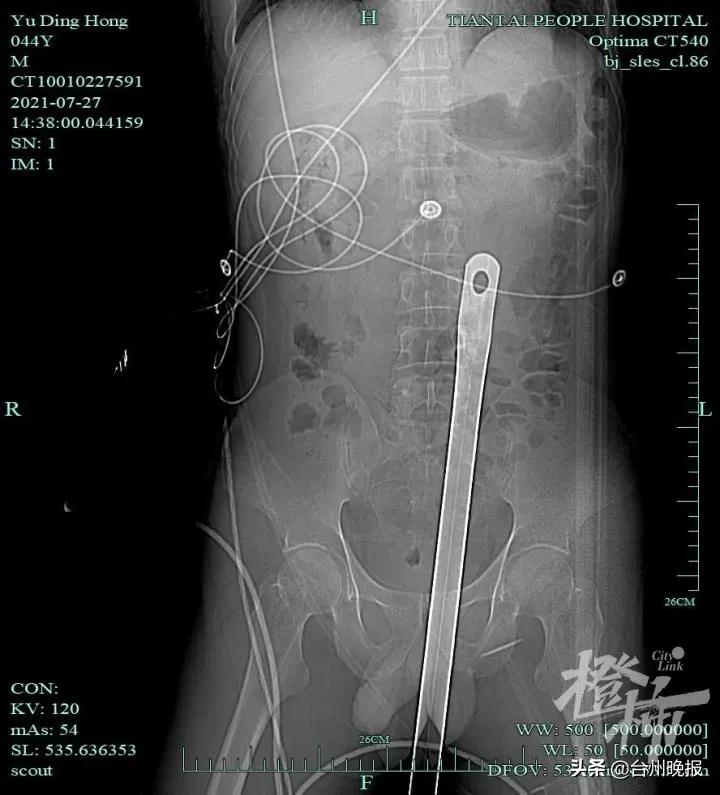

当患者到达医院时,天台县人民医院创伤中心医生第一时间进行查体。因钢管刺入盆腔内太深,患者盆腔损伤情况不明,可能存在血管、肠管损伤及腹腔内大出血,情况危急!在做好保护的情况下,立即为患者行腹部及盆腔CT。结果提示:体内见钢管样异物影,钢管进入盆腔30余厘米,穿透髂骶骨,并被牢牢固定。